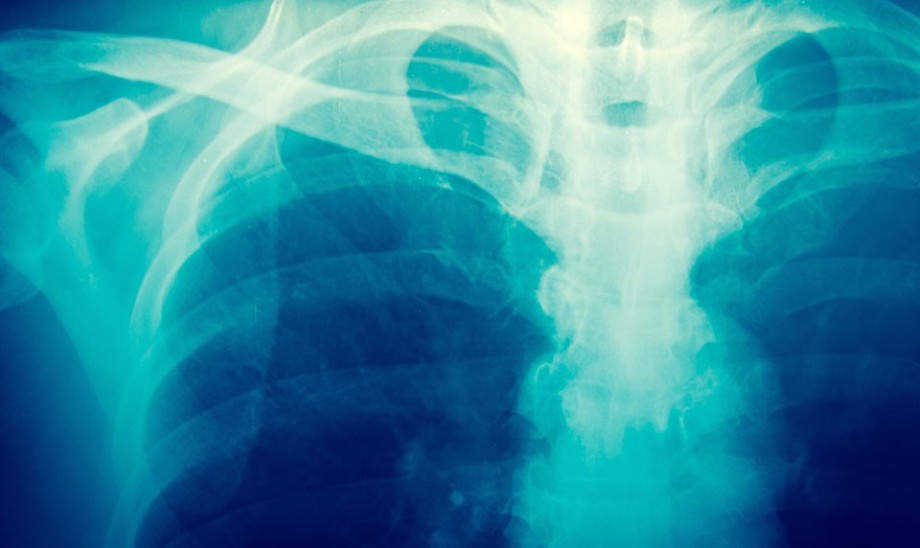

Charakterystyczne objawy występują u mniej niż połowy pacjentów, dlatego u większości choroba wykrywana jest przy okazji diagnostyki innych schorzeń. Podstawą do jej rozpoznania jest zdjęcie RTG. To ono pozwala dostrzec współistniejące ogniska rozrzedzenia i zagęszczenia struktury kostnej oraz pogrubiony i zniekształcony zarys kości długich. Drugim ważnym badaniem jest pomiar ALP (marker kościotworzenia) w surowicy – wzrost aktywności tego enzymu odnotowuje się u większości chorych. Podwyższone mogą być również markery resorpcji kości, może także wystąpić hiperkalcemia (wysoki poziom wapnia we krwi).